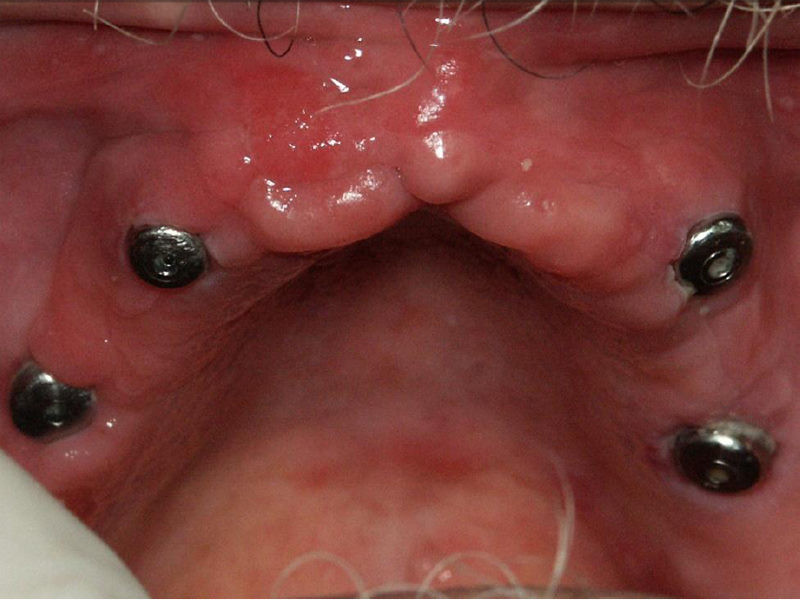

Colocación de cuatro implantes a nivel de maxilar superior

Foto en el cual al paciente se le colocaron cuatro implantes a nivel de maxilar superior